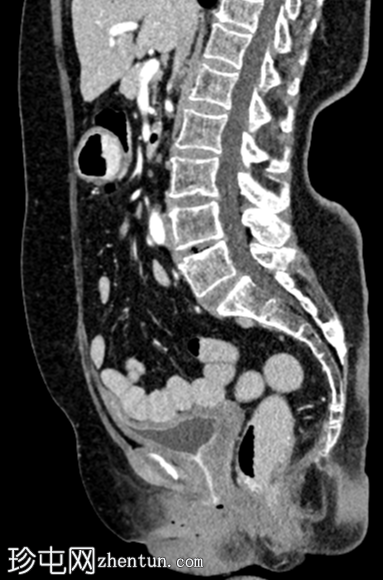

2.png

轴位增强扫描

动脉期

左侧盆壁可见一管状扩张(直径16.5 mm)的充满液体的结构,该结构在S1椎体水平突然向上变窄,然后继续向上延伸,形成轻度强化的纤维条索状结构,直至L5椎体上终板水平。扩张管状结构的尾端逐渐变细,可能终止于阴道穹窿左侧角。在管状结构的尾端可见数个微小的高密度灶,可能为下垂性病灶(其中一个大小为 3.3 mm,315 HU)——可能为结石或钙化。未见其他左侧输尿管样结构。未见左侧膀胱输尿管连接处。

右肾可见多个低密度、无强化的单纯性皮质囊肿和数个高密度、无强化的囊肿——Bosniak II 级。